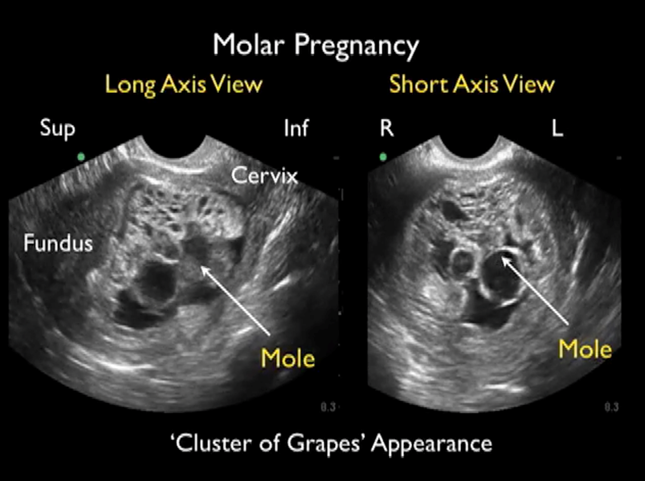

Her vital signs are within normal limits, and her physical exam reveals a well-appearing female with no abnormalities and a non-peritoneal abdomen. Speculum and bimanual exams show a normal, closed cervix without bleeding or discharge. There is no adnexal or uterine tenderness. Results of a serum beta-HCG test are elevated at 148,678. A bedside emergency ultrasound shows a uterus with a snowstorm appearance and multiple grape-like clusters.[1]

Image 1. Short and long axis view of hydatidiform mole (transvaginal ultrasound).

Hydatidiform moles tend to spontaneously occur at extremes of reproductive age and are exceedingly rare. In North America, the incidence is 0.5-1.84 in 1,000 pregnancies; however, in Southeast Asia the incidence is as high as 13 in 1,000 pregnancies.[3] Vaginal bleeding is the most common presenting symptom in molar pregnancy and the diagnosis can be confirmed with serum beta-HCG levels above 100,000 mlU/mL as well as with bedside emergency ultrasound showing a “snowstorm appearance” with grape-like structures representing a vesicular intrauterine mass containing cysts.[1]